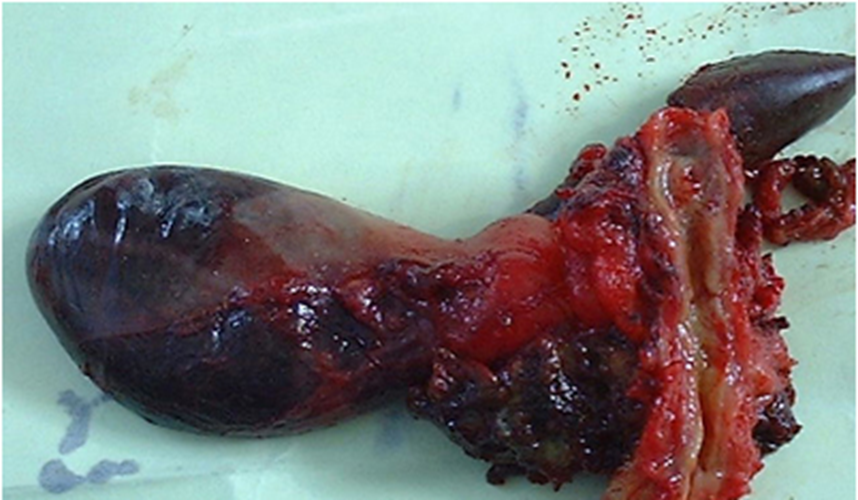

總膽管癌晚期

肝外膽管癌

肝外膽管癌初晚期

肝外膽管癌黃疸表現